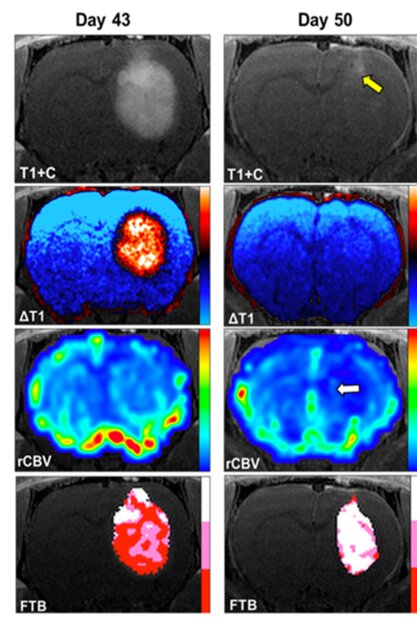

در تحقیقات پیش بالینی، دکتر چیتامبار و دکتر کاتلین اشمایندا کشف کردند که گالیوم مالتولات (GaM) هنگام تجویز داخل وریدی، بهطور قابل توجهی رشد گلیوبلاستوما را در مدل تومور مغزی موشهای صحرایی کاهش میدهد. تحقیقات بیشتر نشان داد گالیوم مالتولات که بهصورت خوراکی در موشهای حامل گلیوبلاستوما تجویز میشود، بهطور قابل توجهی اندازه تومورهای آنها را کاهش داده و بقای آنها را افزایش میدهد.

این شرکت با بیش از یک دهه تجربه در تجزیه و تحلیل کمی تصویربرداری تومور مغز، از جمله تجزیه و تحلیل برای کارآزمایی ملی چند مرکزی مختلف، راه حلهای تجزیه و تحلیل تصویر را برای ارزیابی پاسخ به گالیوم مالتولات ارائه میدهد.